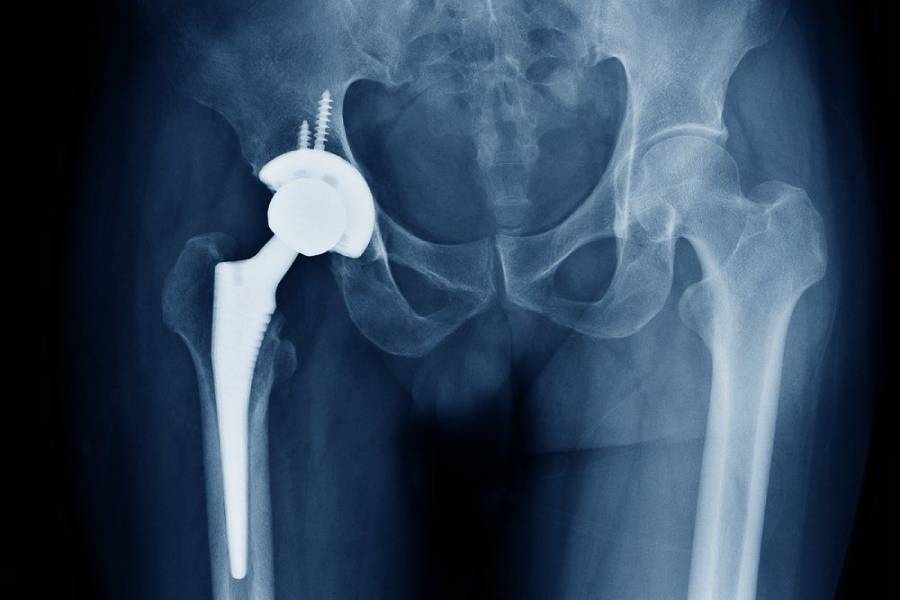

गुडघा प्रत्यारोपण शस्त्रक्रिया ही अतिशय सामान्य समस्या आहे. अनेकदा गुडघा प्रत्यारोपण शस्त्रक्रिया ची गरज अस्थिसुषिरता (osteoporosis) झालेल्या पेशंटवर करण्यात येते.

EXCELLENTTrustindex verifies that the original source of the review is Google. Dr. Prashant Kale recently performed surgery on my left shoulder at Arogyasadan Hospital. The doctors explained the entire process to me thoroughly before the operation. The surgery went very well. The post-operative treatment process was also excellent. The hospital staff is extremely helpful and supportive. Facilities of the highest quality, like those in Pune or Mumbai, are available here. My experience with Dr. Kale has been outstanding.Posted on GoogleTrustindex verifies that the original source of the review is Google. Time per hospital service and cearing pesentPosted on GoogleTrustindex verifies that the original source of the review is Google. One of the best Ortho surgen Doctor I have been visited,I mate with an accident with fractured leg. It was so critical that everyone was worried.My friend recommended me to visit Dr Prashant kale and had the best results ..I was able to walk within 16 days . I personally recommend you to visit ..Posted on GoogleTrustindex verifies that the original source of the review is Google. I have taken a consultation for my mother ...she got best results in few days...I was very anxious about my mother...I already took consultation for her in other hospitals but she didn't get any relief.Posted on GoogleTrustindex verifies that the original source of the review is Google. I visited Arogyasadan Hospital, Ahilya Nagar for orthopedic treatment under Dr. Prashant Kale. He is very experienced, listens patiently, and explains the treatment in simple words. The treatment was effective and satisfactory. Hospital staff is supportive and the facilities are well maintained. I am very satisfied with the overall carePosted on GoogleTrustindex verifies that the original source of the review is Google. My mother-in-law was in a lot of pain and was having trouble for walking. But as per Dr Kale sir's advice I had my mother-in-law Hip replacement done by Dr Kale which gave my mother-in-law a lot of relief. After the operation she can walk very well today. Thanks to Mr and Mrs Dr.Kale sir and madam and your whole hospital staff thank you very much.